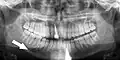

Минимально смещённый перелом правой нижней челюсти. Стрелка отмечает перелом, корневой канал на центральном резце, зубы слева от перелома не соприкасаются